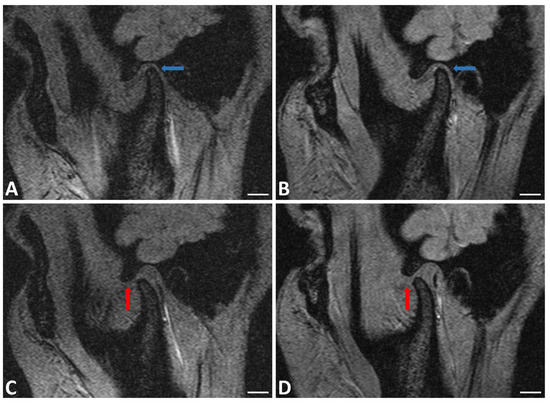

The instrumental analysis performed on TMJs at T0 and T1 is shown in Figure 2.

MRI assessment mostly showed increased excursion of mandibular condyle, recovery from cartilage erosion and increased disk thickness; inversely, condylar and meniscal position improvement were not observed (Figure 2).

The analysis of our data showed an improvement in damage severity index at T1. The significant differences noticed (T0 vs. T1) demonstrate the efficacy of this treatment in the specific cases we treated. This evaluation is confirmed in TMJ imaging made at T1 where it showed increased thickness in both cartilage and disk and condylar excursion increase.

The main objectives of our study were to evaluate the effectiveness of arthrocentesis and SH injection for patients with low and mild temporomandibular joint disorders. The data we collected are in accordance with literature and show improved mouth opening and decreased pain at rest and during mastication. These data were supported also by imaging: MRI showed mandibular condyle excursion increase and thickness increase in both cartilage and disk at T0 and T1. These features make arthrocentesis and sodium hyaluronate infiltration a valid treatment option.

Figure 2. Right TMJ MRI in sagittal plane of patient with the jaw closed at T0 (A) and T1 (B) and open at T0 (C) and T1 (D). Increased disk and cartilage thickness (blue arrows) and increased excursion of mandibular condyle (red arrows) were observed. BAR = 1 cm